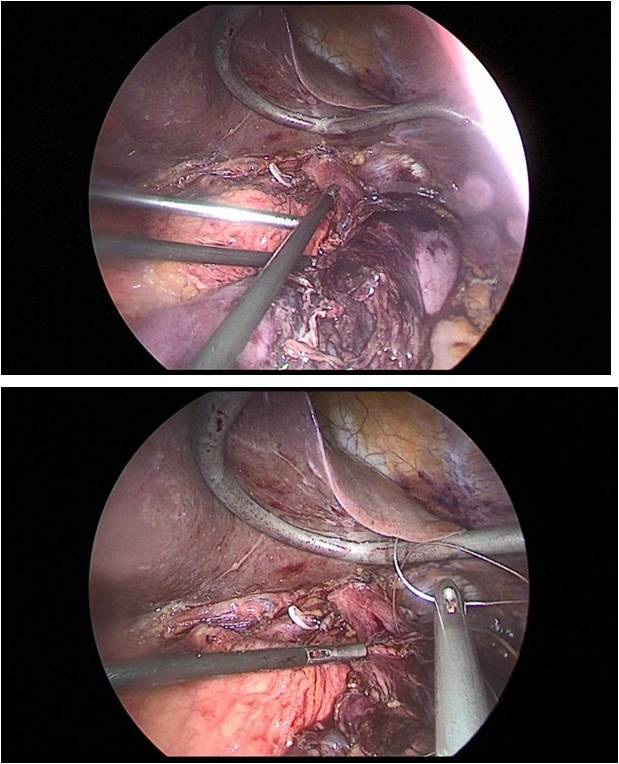

Further, 30 cm away from the ligament of Treitz, the jejunum was transected to apply esophagojejunal anastomosis, then the abdominal part of the esophagus was mobilized, with a pursestring suture with a Vicryl 2.0 thread on the adventitia of the esophagus (Figure 11a,b).

This completed the laparoscopic stage of the operation. Next, a minilaparotomy up to 6 cm long was performed along the white line of the abdomen, retreating 5 cm below the xiphoid process. The stomach was transected at the level of the cardioesophageal fold, after which the jejunum was brought to the abdominal esophagus through the mesocolon window. Then, a circular stapler was inserted through the free edge of the transected jejunum, and a hole was made at a distance of 10 cm from the resected edge along the antimesenteric, into which a circular stapler was inserted and end-to-side esophagojejunostomy was applied (Figure 12).

Figure 12: End-to-side esophagojejunostomy was applied.